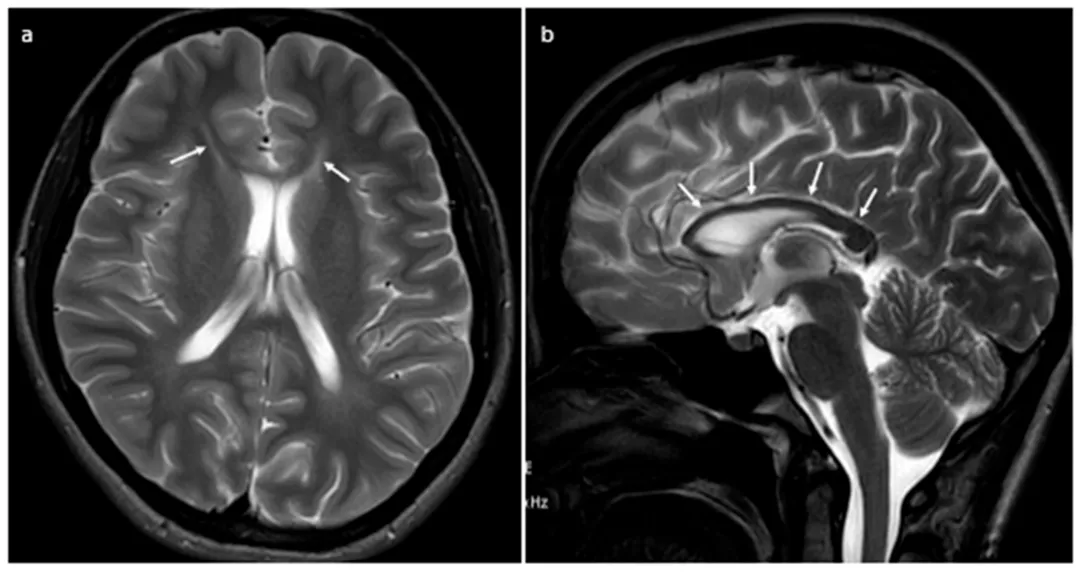

磁共振T2加权成像在轴位(a)和矢状位(b)平面显示:轴位图像可见侧脑室额角尖端T2信号增强,呈“猞猁耳”征(箭头所示);矢状位图像则清晰显示胼胝体萎缩(箭头所示)。